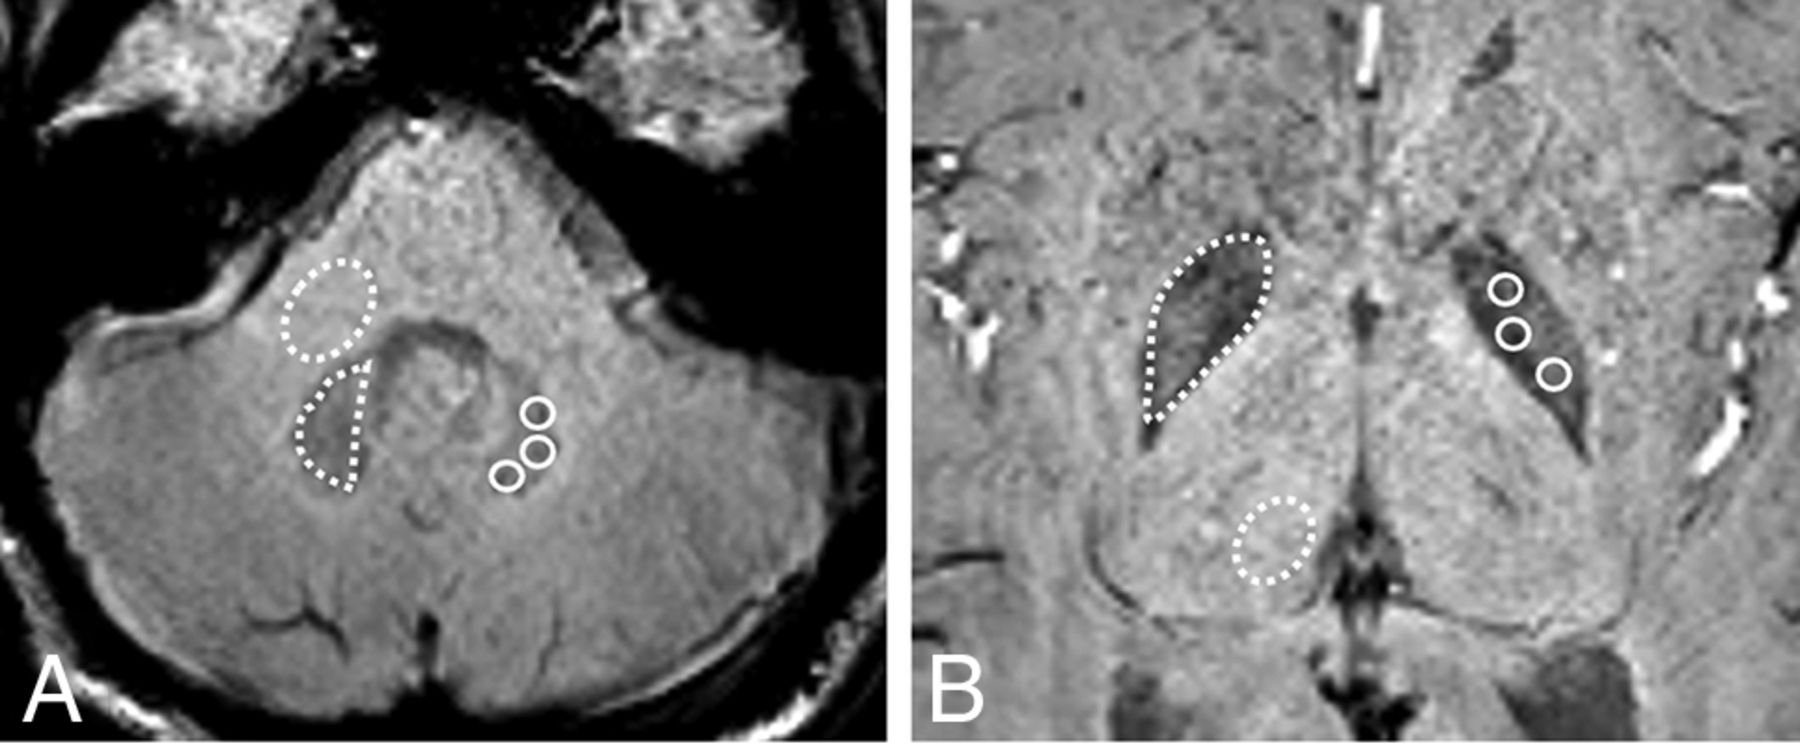

The DN-to-MCP ratios for SWImean and SWImin were lower in those with only linear GBCA administration (SWImean, 0.898 [SD, 0.056]; SWImin, 0.835 [SD, 0.073]) than in both the macrocyclic GBCA group (SWImean, 0.992 [SD, 0.061]; SWImin, 0.928 [SD, 0.064]) and the control group (SWImean, 0.985 [SD, 0.032]; SWImin, 0.925 [SD, 0.037]) (adjusted P value < .001). No significant differences in the DN-to-MCP ratio for SWImean and SWImin were noted between the macrocyclic GBCA group and the control group (P = .595 and .829, respectively). The mean DN-to-MCP ratios on T1WI in the linear GBCA group (0.986 [SD, 0.073]) were also higher than those in the non‐GBCA group (0.926 [SD, 0.042]) and the macrocyclic GBCA group (0.930 [SD, 0.043]) (adjusted P value < .001) (Fig 2). A moderate negative correlation was identified between the DN-to-MCP ratio for SWImean and SWImin and the number of linear GBCA administrations (SWImean, r = –0.43 and P = .005; SWImin, r = –0.38 and P = .011) (Fig 3).

Boxplots of the mean DN-to-MCP ratios on SWI and T1WI among the linear GBCA, macrocyclic GBCA, and control groups. The error bars for boxplots represent the minimum and maximum data points within each group, and the Middle box represents the 25th, 50th, and 75th percentiles of the data within each group.

The GP-to-Th ratios for SWImean and SWImin were lower in those with only linear GBCA administration (SWImean, 0.765 [SD, 0.041]; SWImin, 0.751 [SD, 0.038]) than in both the macrocyclic GBCA group (SWImean, 0.804 [SD, 0.047]; SWImin, 0.793 [SD, 0.045]) and the control group (SWImean, 0.857 [SD, 0.052]; SWImin, 0.841 [SD, 0.048]) (adjusted P value < .001). No significant differences of the GP-to-Th ratio for SWImean and SWImin were noted between the macrocyclic GBCA group and the control group (P = .503 and 0.778, respectively). Mean GP-to-Th ratios on T1WI in the linear GBCA group (1.001 [SD, 0.072]) were also higher than in the non‐GBCA group (0.953 [SD, 0.047]) and the macrocyclic GBCA group (0.958 [SD, 0.049]) (adjusted P value < .001). A moderate negative correlation was identified between the GP-to-Th ratio for SWImean and SWImin and the number of linear GBCA administrations (SWImean, r = –0.39, P = .009; SWImin, r = –0.33, P = .017).The Pearson correlation coefficient revealed no significant correlation between SWI/T1WI–derived values and the mean time interval among MR imaging, total GBCA dose, and age (all P > .05). There was no significant difference in the SWI/T1WI–derived SI ratios regarding sex, intrinsic disease, and a history of radiation or chemotherapy (all P > .05). Multivariate linear regression analyses derived from univariate analysis demonstrated that SWImean and SWImin ratios were associated with the number of linear GBCA administrations (adjusted R2 for the model = 0.185) (SWImean; β = –0.022, P = .015; SWImin; β = –0.026, P = .028). Additionally, no significant correlation was noted between SWI-derived values and age in the control groups (SWImean: r = –0.14, P = .15; SWImin: r = –0.11, P = .24).